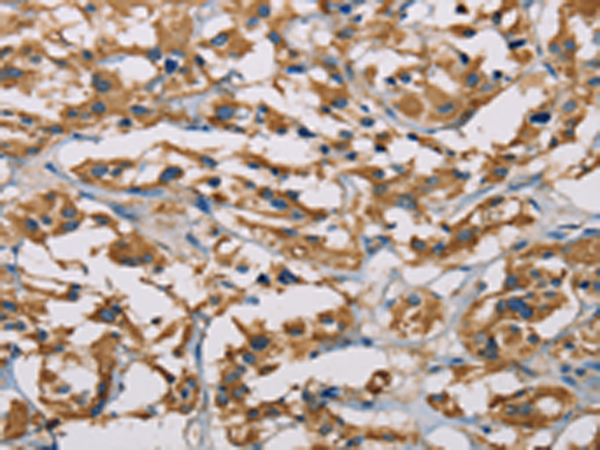

分类: 科研抗体货号: P08025别名: SK 2; SK-2; SPK 2; SPK-2应用: WB,IHC反应种属: Human, Mouse